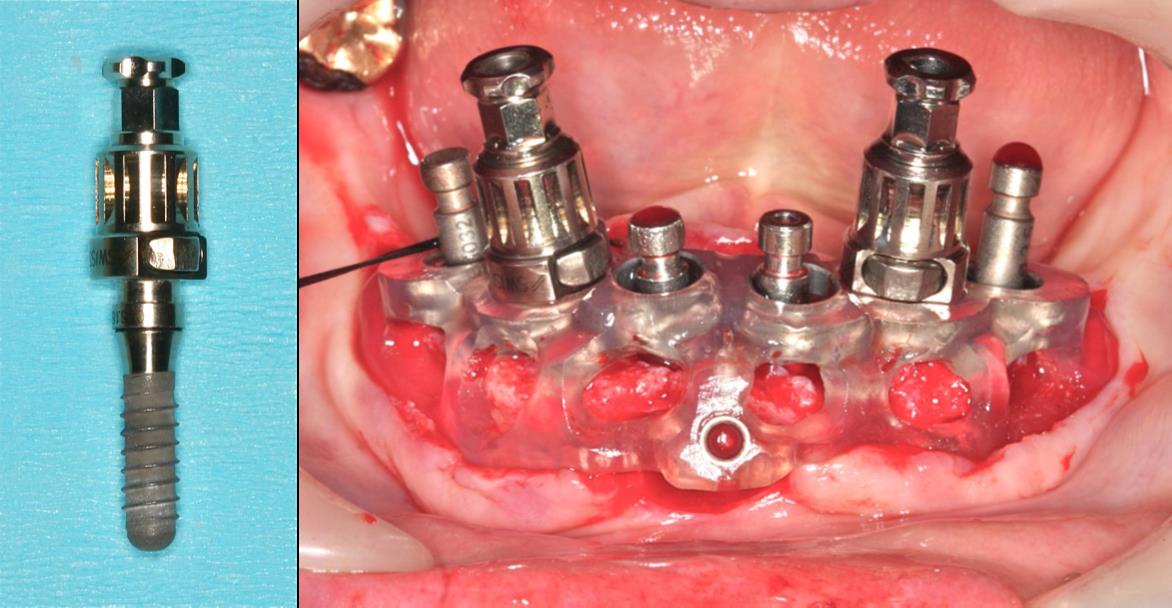

場合によってはフライスドリルで直接骨採取も可能

温故知新 従来のマウントでガイドを固定している